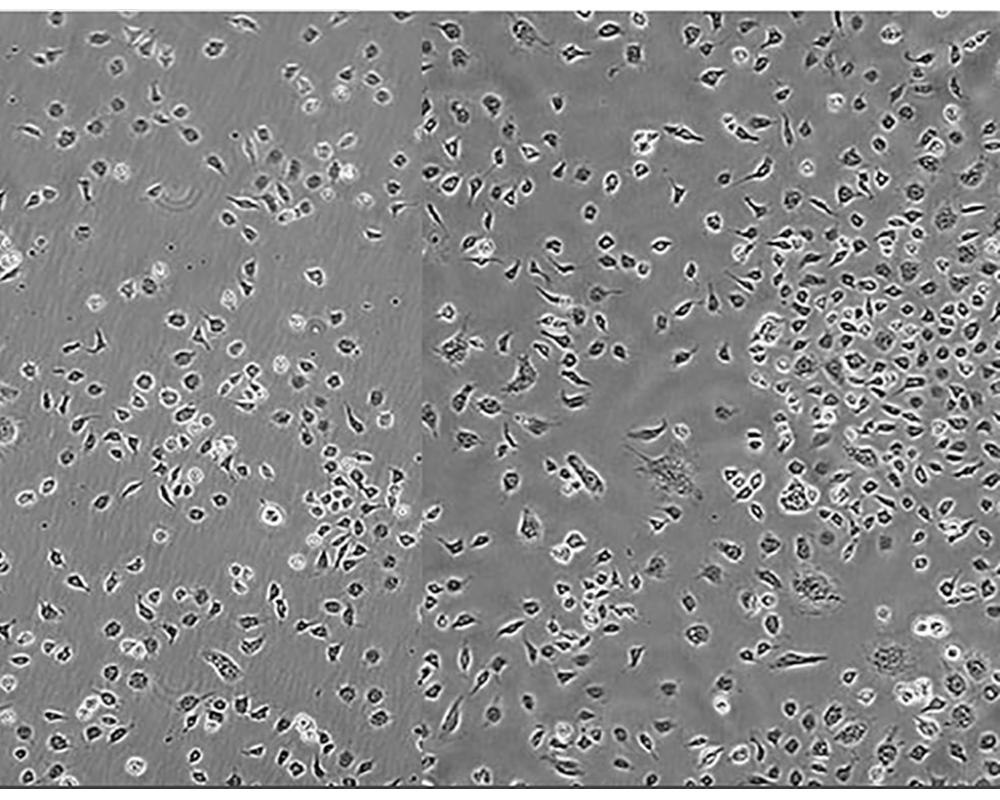

C6細(xì)胞

產(chǎn)品名稱 C6細(xì)胞

組織來源 惡性神經(jīng)膠質(zhì)瘤;雄性;Wistar Furth

細(xì)胞種屬 rattus norvegicus, rat

生長特性 adherent

形態(tài)特征 fibroblast

細(xì)胞描述 膠質(zhì)細(xì)胞株C6是由Benda等用N-nitrosomethylurea誘導(dǎo)的大鼠膠質(zhì)瘤克隆,并經(jīng)過一系列的體外培養(yǎng)和動物傳代交替后建成的。 當(dāng)細(xì)胞從低密度生長到滿瓶時,S-100產(chǎn)量增加10倍。 膠質(zhì)細(xì)胞株C6是由Benda等用N-nitrosomethylurea誘導(dǎo)的大鼠膠質(zhì)瘤克隆,并經(jīng)過一系列的體外培養(yǎng)和動物傳代交替后建成的。 當(dāng)細(xì)胞從低密度生長到滿瓶時,S-100產(chǎn)量增加10倍。